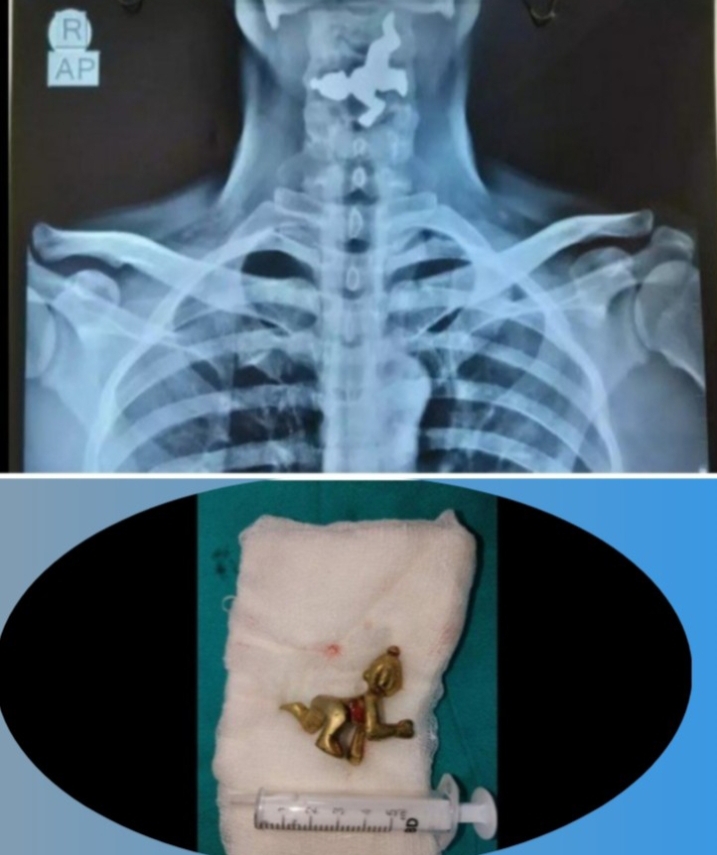

ಈ ವ್ಯಕ್ತಿ ಪ್ರತಿ ದಿನ ದೇವರ ಪೂಜೆ ಮಾಡಿದ ಬಳಿಕ ತೀರ್ಥ ಸೇವನೆ ಮಾಡುವ ಅಭ್ಯಾಸ ಮಾಡಿಕೊಂಡಿದ್ದರು. ಎಂದಿನಂತೆ ಪೂಜೆ ಮಾಡಿದ ಬಳಿಕ ತೀರ್ಥ ಸೇವಿಸುವಾಗ ಈ ಘಟನೆ ನಡೆದಿದೆ. ಹೌದು.. 45 ವರ್ಷದ ವ್ಯಕ್ತಿಯೊಬ್ಬ ನಿತ್ಯ ಮನೆಯಲ್ಲಿ ಪೂಜೆ ಮಾಡಿ, ದೇವರ ತೀರ್ಥ ಸೇವಿಸಿ, ಎಂದಿನಂತೆ ಪೂಜೆ ನೆರವೇರಿಸಿದ ನಂತ್ರ, ತೀರ್ಥ ಕುಡಿಯೋ ಸಂದರ್ಭದಲ್ಲಿ 50 ಗ್ರಾಂ ತೂಕದ ವಿಗ್ರಹ ಕೂಡ ನುಂಗಿ ಬಿಟ್ಟಿದ್ದಾನೆ. ಬಳಿಕ ಆತನಿಗೆ ಗಂಟಲು ನೋವು ಮತ್ತು ಗಂಟಲು ಊತ ಉಂಟಾಗಿದೆ. ಕೂಡಲೇ ಸ್ಥಳೀಯ ವೈದ್ಯರನ್ನು ಆತ ಸಂಪರ್ಕಿಸಿದ್ದಾರೆ.

ಎಂಡೋಸ್ಕೋಪ್ ಮಾಡಿರುವ ವೈದ್ಯರು ಬಾಲಕೃಷ್ಣನ ಮೂರ್ತಿಯ ಕಾಲು ವ್ಯಕ್ತಿಯ ಆಹಾರ ನಾಳದಲ್ಲಿ ಸಿಲುಕಿಕೊಂಡಿರುವುದನ್ನು ಪತ್ತೆ ಮಾಡಿದ್ದಾರೆ. ನಂತರ ಇಎನ್ಟಿ ವಿಭಾಗದ ವೈದ್ಯರು ಶಸ್ತ್ರ ಚಿಕಿತ್ಸೆ ಮಾಡಿ ಗಂಟಲಿನಲ್ಲಿ ಸಿಲುಕಿದ್ದ ಕೃಷ್ಣನ ವಿಗ್ರಹವನ್ನು ಯಶಸ್ವಿಯಾಗಿ ಹೊರತೆಗೆದಿದ್ದಾರೆ.

ಗಂಟಲಿನಲ್ಲಿ ಸಿಲುಕಿದ್ದ ಕೃಷ್ಣನ ಮೂರ್ತಿಯನ್ನು ಹೊರತೆಗೆಯುವುದು ವೈದ್ಯರಿಗೆ ಸುಲಭದ ಕೆಲಸವಾಗಿರಲಿಲ್ಲ. ಅದರಲ್ಲೂ ಮೂರ್ತಿಯ ಕಾಲು ಆಹಾರ ನಾಳದಲ್ಲಿ ಸಿಲುಕಿತ್ತು. ಸದ್ಯ ವ್ಯಕ್ತಿ ಆರೋಗ್ಯವಾಗಿದ್ದು ಚೇತರಿಸಿಕೊಳ್ಳುತ್ತಿದ್ದಾನೆ ಎಂದು ವೈದ್ಯರು ಮಾಹಿತಿ ನೀಡಿದ್ದಾರೆ.